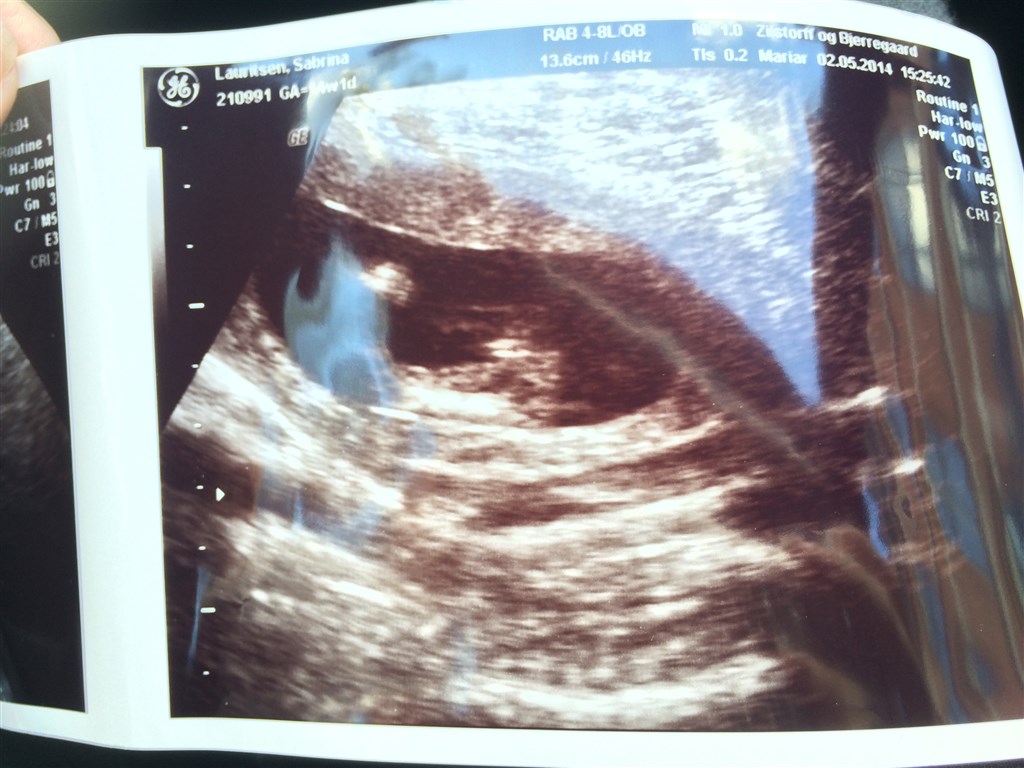

Jeg har lige været inde hos scanningskliniken på Østerbro, hvor jeg fik 99% sikkerhed på at jeg ..... Venter mig en lille pige!

Der var kun 1% for at der var en dreng, men jeg har selvfølgelig fået en ny tid for den sidste procent.. Men jeg kunne godt begynde stille og roligt at købe lyserøde ting :-)

Der står 14+1 på billederne

Nej, de fleste private klinikker garanterer fra 14+0